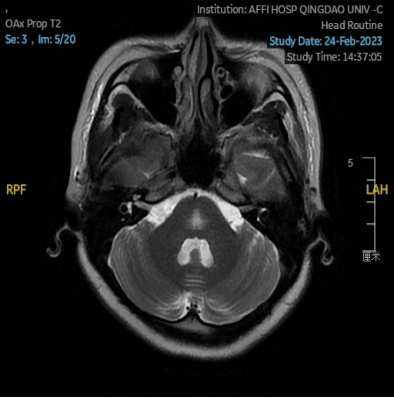

2023.02.24颅脑MR平扫示双侧基底节区及桥脑异常信号,考虑渗透性脱髓鞘综合征,见图3。

图3 2023.02.24颅脑MR成像示双侧基底节区及桥脑见对称性片样长T1长T2信号,FLAIR呈高信号。脑室、脑池、脑沟、脑裂未见明显异常。中线结构居中。

图片